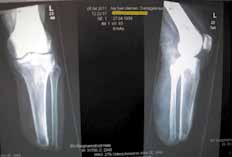

Sehr lange Unterschenkelstümpfe (kurz oberhalb der Spongiosa der distalen Tibia) sind auf die Dauer wegen der Gefahr zunehmender trophischer Störungen über die Jahre auch bei sehr geringem Endkontakt in der Prothese problematisch (Abb. 11). Viele Jahre scheint ein langer US-Stumpf gut versorgbar zu sein, wenn die Amputation im Kindesalter stattfindet und wenn Tibia- und Fibulaende sich fast auf gleicher Höhe befinden und somit eine breitere Auflagefläche für den Endkontakt darstellen (Abb. 12). Gewebe und arterielle Durchblutung stellen sich offenbar im Kindesalter auch besser auf die Gesamtsituation ein. Allgemein gilt aber: Der beste Unterschenkelstumpf ist der, der mit Muskulatur unter physiologischer Vorspannung gedeckt ist.

Der kurze Stumpf (proximales Drittel) bedeutet im Knochen mehr Spongiosa. Das wiederum bedeutet wegen der besseren Lastverteilung eine höhere Stumpfendbelastbarkeit um 80 bis 90 %. Höhere Stumpfendbelastbarkeit bedingt mehr Propriozeption. Somit wird der Verlust besserer Biomechanik gegenüber dem mittellangen Stumpf teilweise ausgeglichen. Die Rehabilitation gestaltet sich in der Regel unkompliziert. Die Entfernung der Fibula ist kein Nachteil für die prothetische Versorgung, da der Stumpf eine Dreiecksform besitzt. Im Gegenteil, das Fibulaköpfchen wird nicht prominent, was die Kurzstumpfversorgung erleichtert.